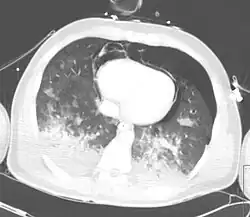

| CT scan showing pneumopericardium with pneumomediastinum, pneumothorax, hemothorax, and pulmonary contusion after severe chest trauma[1] | |